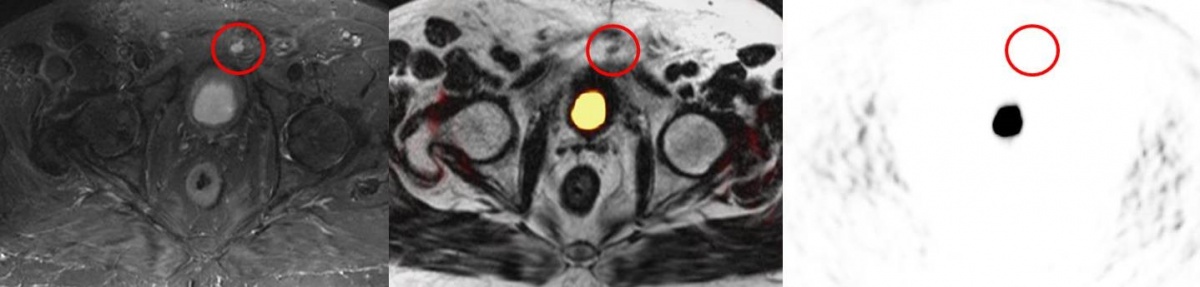

Die Expression von PSMA in der Prostata steigt mit zunehmender Tumoraggressivität, während es in blandem Prostatagewebe kaum nachweisbar ist [8, 34, 37]. Deshalb wird zunehmend an der Entwicklung von Hybridmethoden gearbeitet, die die PSMA PET und die mpMRT in einem Untersuchungsdurchgang durchführen können, um die hohe Sensitivität der MRT mit der metabolischen Aussage der PET zu verbinden [23, 26, 36]. Dies ist besonders im Hinblick auf eine Unterschätzung des Tumorgrades sowie für die Optimierung der TNM-Klassifikation prätherapeutisch von erheblicher Bedeutung. Meist wird das PSMA an den Tracer 68Ga gekoppelt, seit neuem auch an 18F [35].

Die Magnet-Resonanz-Tomographie, speziell die multiparametrische Hochfeld-MRT (3T), ist aktuell die marktverfügbar sensitivste morphologische bildgebende Methode. Es liegt nahe, die hohe Sensitivität der MRT mit einem hochspezifischen Tracer zu kombinieren. Daher ist der direkte Vergleich von PSMA PET/CT und PET/MRT (multiparametrisch) von erheblichem Interesse für künftige Untersuchungen [6]. Es ist bereits jetzt unbestritten, dass in Zukunft die Hybridverfahren PET/CT – PET/MRT bessere Ergebnisse bringen als die einzelnen morphologischen Methoden [33].